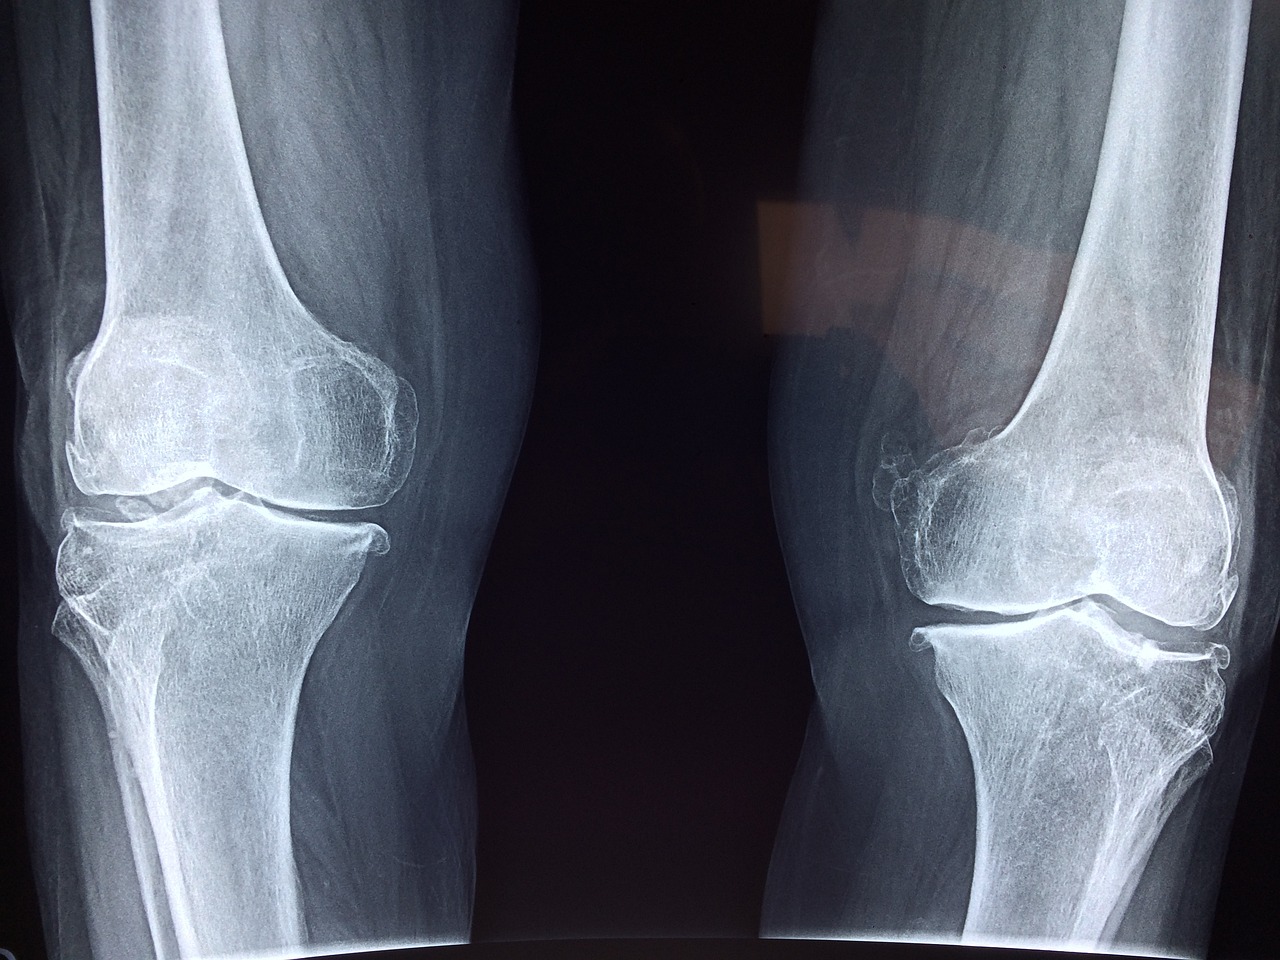

4. 관절의 변형

퇴행성 관절염이 진행되면 관절의 모양이 변형될 수 있습니다.

예를 들어, 손가락 마디가 두드러지거나 구부러지거나, 무릎이 안쪽으로 꺾이거나, 엉덩이가 비대칭적으로 되는 등 여러 현상이 나타날 수 있습니다.